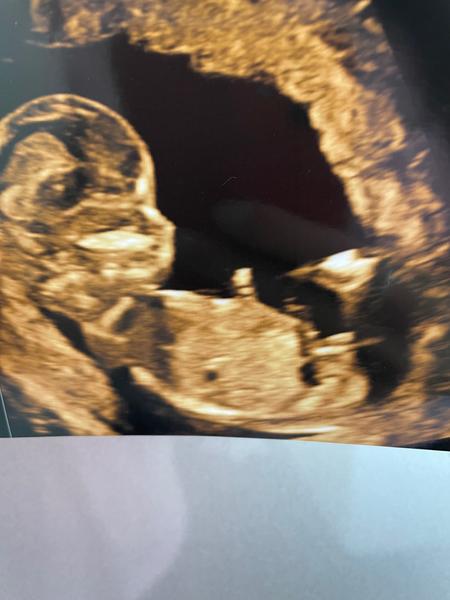

Je možné odhadnout pohlaví ve 14. týdnu těhotenství?

Tipne si někdo pohlaví? Je to vůbec takto možné nebo to je nožička a pohlaví vidět nejde? Je mi jasné, že je brzo, jen jsem hrooozný zvědavec 🙂